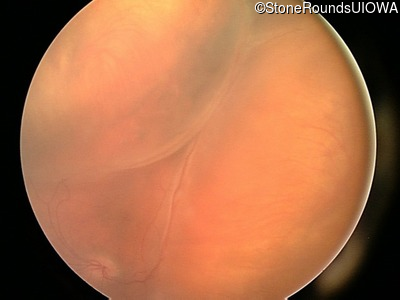

Visit at age: 3 years

Fundus Photography - Right - Hand Motion

Exemplar